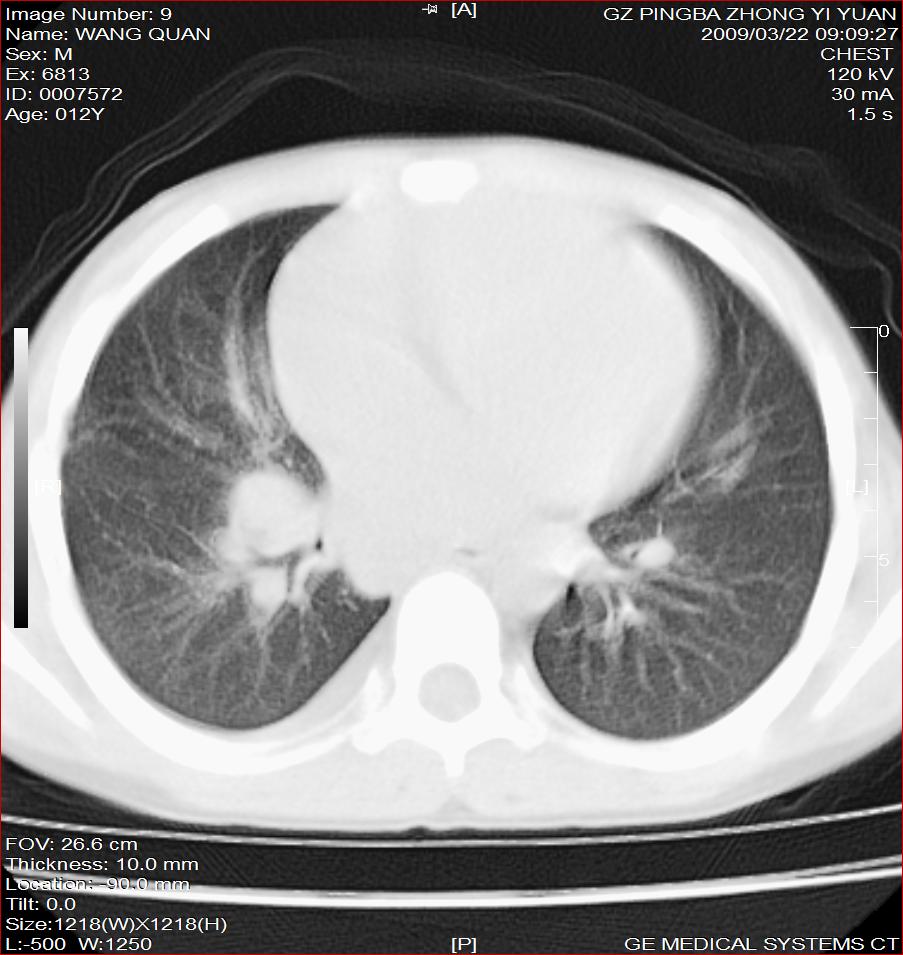

以下是引用随光逐影在2009-3-23 8:12:00的发言:[br]1)右肺门及纵隔淋巴结结核。2)两肺急性血行播散型肺结核可能。3)右侧支气管内膜结核?建议必要时行纤支镜检查。4)右侧少量胸腔积液。